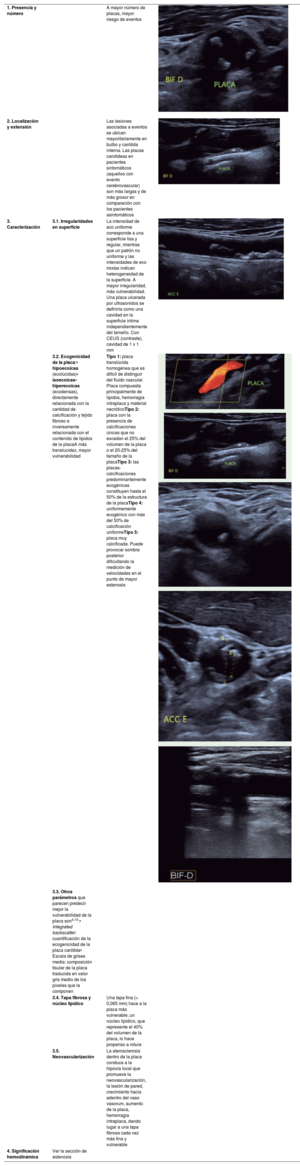

Las placas tienen mejor especificidad para la valoración del RCV que el GIM y pueden ser consideradas como predictores de aumento del RCV en algunos casos.